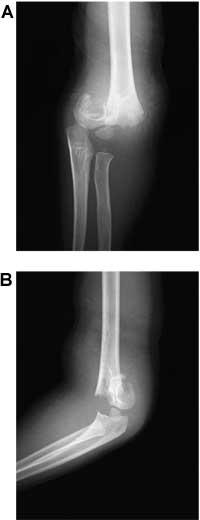

理学療法士実地問題 - 第46回 午後

8歳の男児。公園の滑り台から誤って転落して左手をつき、痛みのために救急外来を受診した。左肘関節中枢部に疼痛、腫脹および変形が認められる。初診時の左肘のエックス線写真ABを示す。急性期の合併症で起こりにくいのはどれか。